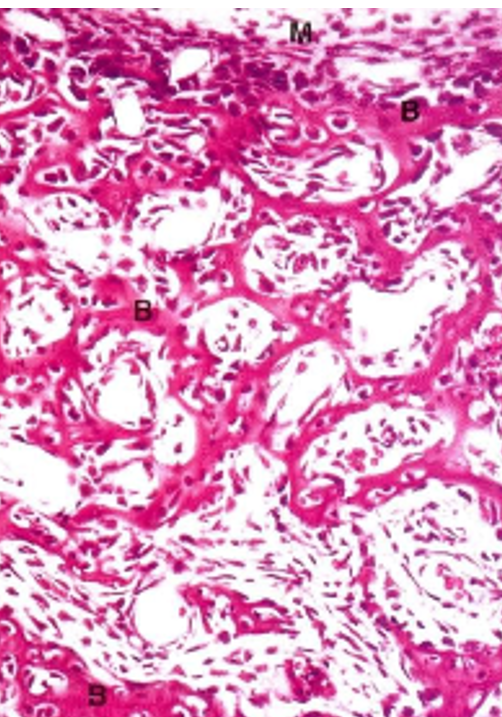

De acordo com a conformação microscópica da Matriz extracelular, dois tipos de tecido ósseo são identificados, o tecido ósseo lamelar ou secundário, sendo típico do tecido ósseo compacto maduro (Fig. 1); e tecido ósseo não-lamelar ou primário, observado no tecido ósseo imaturo (Fig. 2).

Fig. 2 – OSSIFICAÇÃO ENDOCONDRAL

Aumento de 10x

Coloração picrosirius